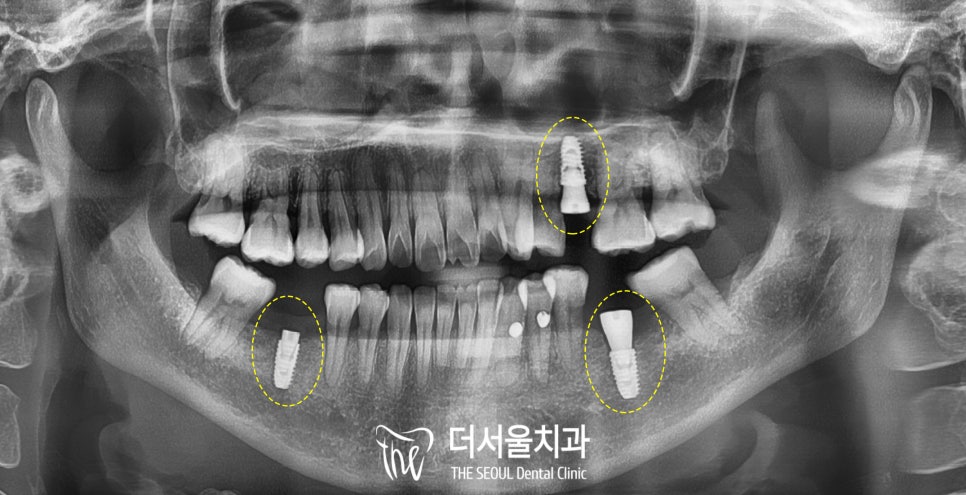

구강을 살펴보면

곳곳에

충치가 생긴 곳이 보이네요.

그런데 그중에서도

제가빨간색으로 표시해둔 부분은

우식의 깊이도 깊고 범위도 넓어서

빠른 해결이 필요한 상황이었습니다.

또한 노란색으로 표시해둔 부분은

뿌리가 부러진 채로

잇몸에 박혀있어서

발치를 하고 그 기능을 대체할

디지털 임플란트를 해주는 게

좋을 것으로 판단했습니다.

아랫니도 마찬가지인데요,

오른쪽 아래는 잔존 치근이 남아있고

왼쪽 아래는 이가 빠진지 시간이 오래되어

치조골의 폭이 좁아져있습니다.